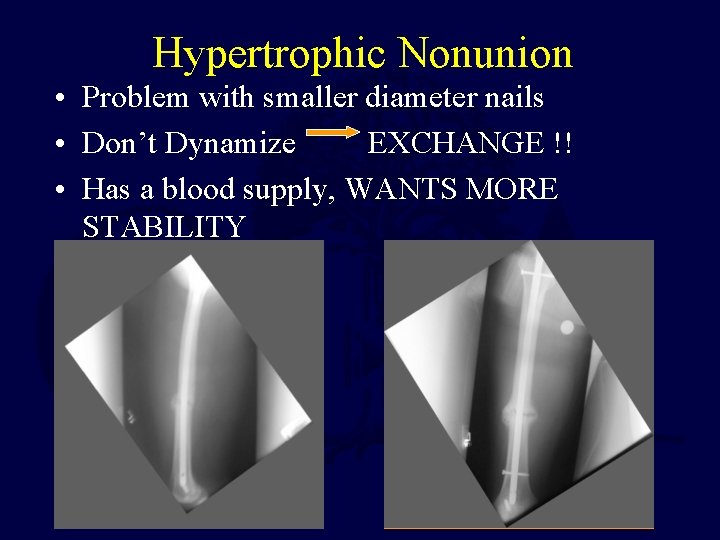

Hypertrophic Nonunion • Problem with smaller diameter nails • Don’t Dynamize EXCHANGE !! • Has a blood supply, WANTS MORE STABILITY